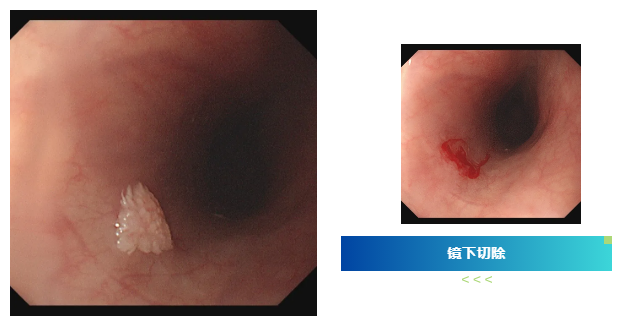

检查过程中,内镜医生有了意外发现:小张的食管部位长有一个形似花朵的乳头状瘤。吕主任介绍,食管乳头状瘤在临床中并不常见,尤其是在年轻男性群体中更为少见,其发病多与病毒感染相关,比如HPV病毒。幸运的是,发现及时,肿瘤尚处于早期阶段,医生随即为小张进行了内镜下切除术,整个过程顺利完成。

吕主任表示,像小张这样的案例并非个例。很多年轻人对消化道的轻微不适不以为意,觉得“忍忍就过去了”,殊不知一些看似普通的症状,可能是身体发出的健康警报。食管乳头状瘤虽然恶变概率相对较低,但如果长期忽视,也存在病变风险。而胃肠镜检查作为消化道疾病筛查的“金标准”,能够直接观察到食管、胃、肠道黏膜的细微变化,实现早发现、早诊断、早治疗。